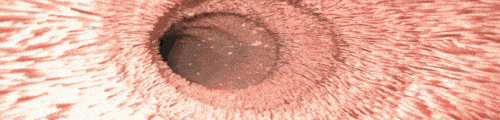

<장속 흡수하는 위치 융모모습>

<융모를 벗겨내니 수분량증가 지용성흡수줄어>

장속을 살펴보았다 바로 융모라는 털이 문제였다 우리는 입으로 음식을 먹지만 장은 융모라는 털로 영양분을 섭취하고 변을 이동시킨다

융모에서 영양분이나 수분,산소를 90% 흡수한다 흡수된 수분과 산소는 혈액을 타고 이동해서 쓰임이 다하면 소변이나 땀으로 배출된다

융모의 노폐물을 벗겨내면 수분과 산소흡수가 더 잘된다 그렇다면 가스가 차지 않을것이며 융모가 수분으로 팽창하면 물과 기름 흡수가 줄어든다는 결론이 나온다

실제로 이 융모를 벗겼을때 수분은 200g 올라가고 지용성분은 600g이 줄었다  식이섬유나 유산균을 먹었을때 보다 가스가 줄었고 지용성흡수가 적어져 가스차고 배나오는 증상을 해결했다